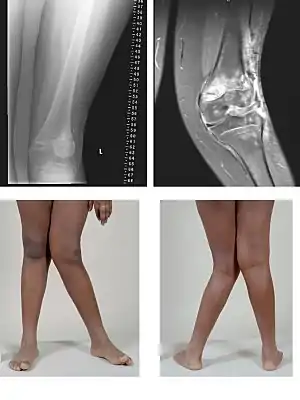

پای ضربدری،ژنووالگوم (به انگلیسی: Genu Valgum) همانند پای پرانتزی یک تغییر شکل یا دفورمیتی در مفصل زانو است.در یک فرد طبیعی در حالت ایستاده زمانیکه بین زانوها فاصله ای وجود نداشته باشد، قوزکهای مچ پا نیز هیچ گونه فاصله ای ندارند.اگر با کنار هم بودن زانوها، بین مچ پاها یا قوزکها فاصله ایجاد شود پای ضربدری گویند.نکته مهم در حالت پای ضربدری این است که انحراف ساق پا نسبت به وضعیت طبیعی به سمت بیرون افزایش می یابد.

پای ضربدری خوش خیم در کودکان در سنین سه تا پنج سالگی شایع است.پای ضربدری(والگوس زانو) در این کودکان غالباً با کف پای صاف همراه است و میتوان این حالت را با کفش طبی اصلاح کرد، در اکثر موارد این تغییر شکل تا شش سالگی اصلاح می گردد.[1] البته بهتر است که یک بررسی از جهت اینکه بیماری خاصی وجود ندارد به عمل آید.

درجات پای ضربدری

- خفیف

- متوسط

- شدید